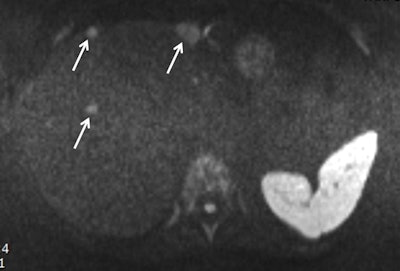

One cornerstone of conventional liver MRI is delayed contrast-enhanced (CE) imaging. In a conventional protocol, acquisition of these sequences takes 15 seconds, which can be reduced to three to five seconds. The extra time gained between delay points should be used to acquire other data, such as T2-weighted imaging or diffusion-weighted imaging (DWI), which conventionally is done before or after CE sequences.

DWI is another useful MRI technique for liver imaging. However, 20% to 30% of radiologists don't include it because they don't understand its benefits, Lauenstein noted.

"DWI has a two-minute acquisition time and provides similar information to T2-weighted imaging, meaning you can skip some T2 sequences," he said. "Importantly, DWI is an all-in-one sequence which provides different information."

He suggested that in a 10-minute protocol, all CE sequences could be avoided. DWI, T2, and T1 sequences should be prioritized instead. He also highlighted some of the pitfalls of the shorter MRI protocol for liver questions: While sensitivity remains high for any clinically relevant data, there will be some loss of specificity. When results from the short protocol are abnormal, the MRI scan will need to be repeated with standard sequences. This begs the question: Who should receive the short protocols and who gets the longer ones?